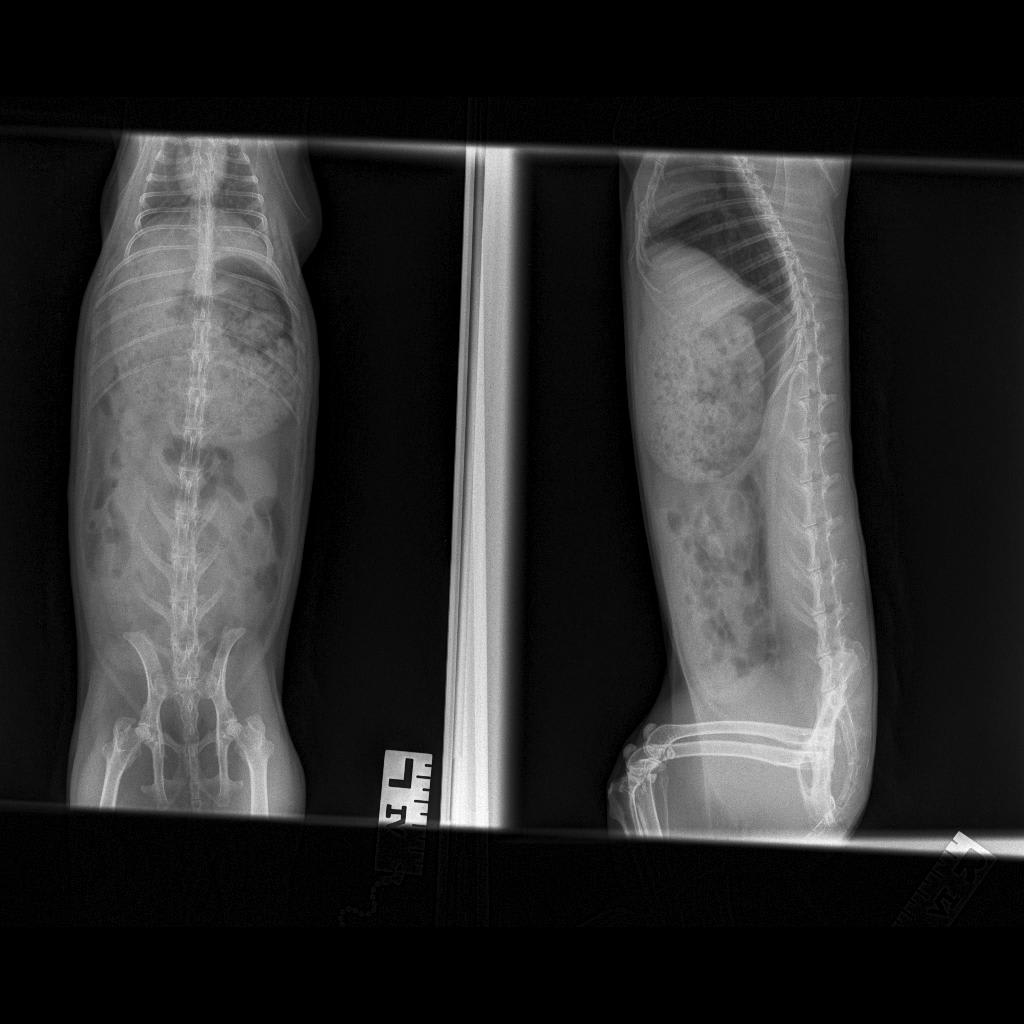

Got suggested therapy with meloxicam and glucosamine for my bunny's hip. There isn't a specialized glucosamine for bunnies, and my vet suggested Flexadin tablets. 1/4 of it a day for my 2kg bun. The ingredients per tablet (2 g): Glucosamine HCI 500mg; Chondroitin sulfate 400 mg; Harpagophytum procumbens (devil's claw) 150 mg; Manganese sulfate (provides 10 mg of manganese) 31.2 mg; Contains poultry flavour (vegetable origin). Is this safe? Attached x-ray and product. I appreciate your help.